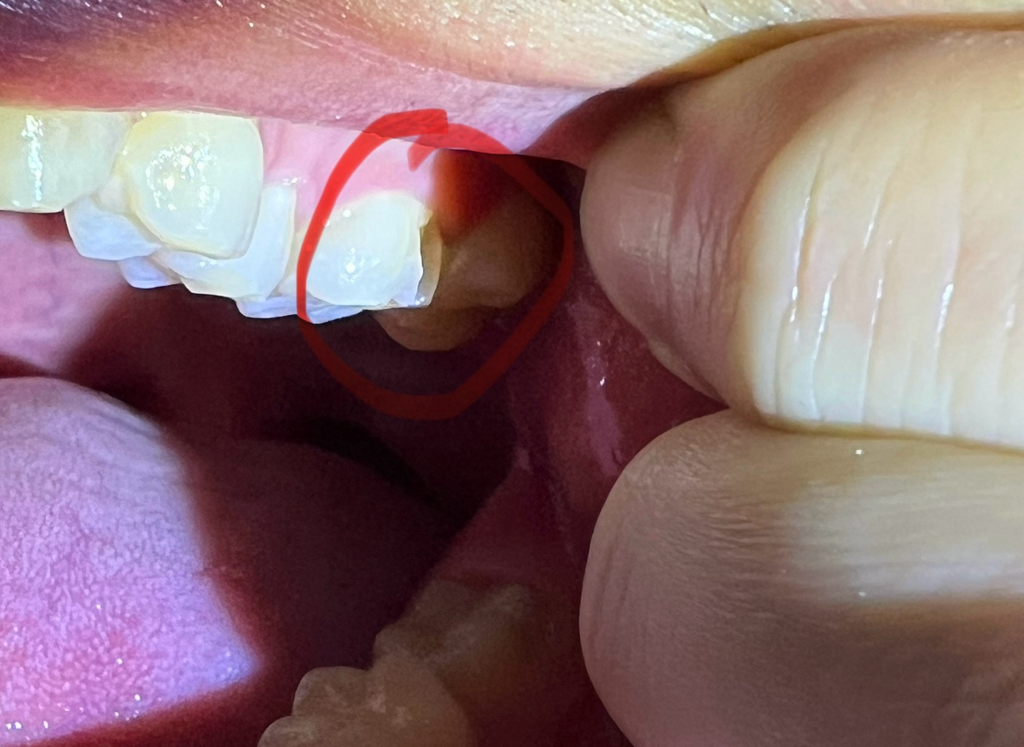

안녕하세요 어제 저녁을 먹다가 돌을 씹었는지

뿌득 하는 소리와 함께 현제 사진과 같은 상태로

어금니 옆부분이 깨진거같은데요

• 1번 째 사진

말씀하신 것처럼 어금니 옆면 표면이 깨져나가 있습니다. 치아의 가장 바깥층을 법랑질이라고 하는데 법랑질 부위가 없거나 얇아지면 내부 상아질, 치수(치아 신경)가 드러나면서 시릴 수 있습니다. 시간이 지남에 따라 경화상아질이라는 새로운 층이 생겨 시린 증상이 너무 심하지 않도록 치아 자체가 방어벽을 형성하기도 하지만 시린 증상이 심하다면 치과에서 치료를 받는 편이 좋습니다

해당 부위는 아주 깊거나 크게 깨지지는 않았으나 충전재료가 잘 떨어지는 위치이므로 치과의사의 판단에 따라 다를 수는 있으나 레진으로 떼워줄 수도 있고, 크라운을 하자고 할 수도 있습니다.